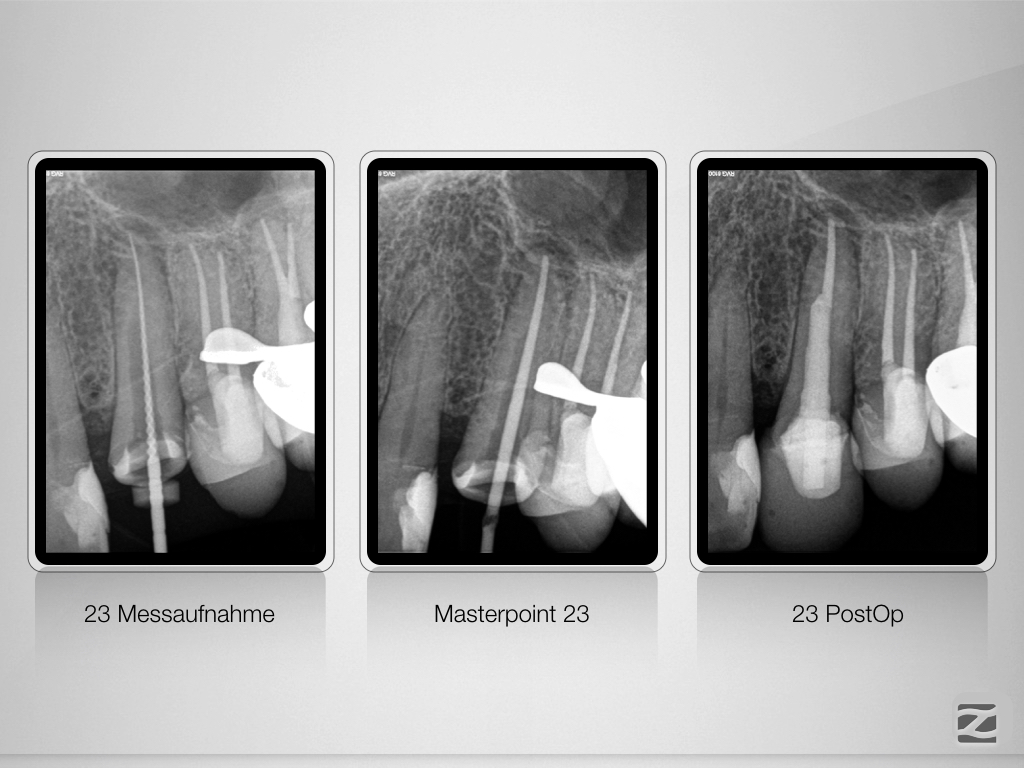

Keine Angst vor bösen Stiften!